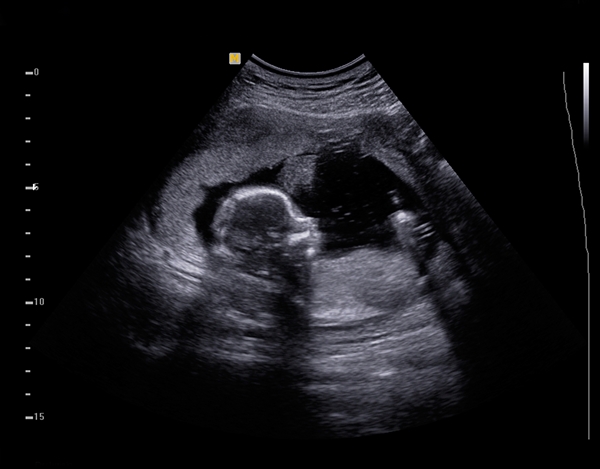

อัลตราซาวนด์ คือการตรวจด้วยคลื่นเสียงความถี่สูง มีความปลอดภัย และสามารถทำได้บ่อยครั้งเท่าที่ต้องการ ปัจจุบันพัฒนาการของเครื่องอัลตราซาวนด์ก้าวหน้าเป็นอย่างมาก จากปกติ 2 มิติ พัฒนาสู่ 3 และ 4 มิติ ทำให้คุณพ่อคุณแม่สามารถเห็นหน้าลูกได้ชัด แต่จะเลือกวิธีไหนดี คุณหมอจะเป็นผู้แนะนำ

ตรวจอัลตราซาวนด์ภาพ 2 มิติ คือ เป็นภาพตัดขวางทีละภาพ ตามแนวของคลื่นเสียงความถี่สูงที่ส่งออกไปในแนวระนาบ (มิติที่ 1 คือความกว้าง มิติที่ 2 คือ ความยาว) ภาพที่จะได้ออกมาจะเป็นภาพแบบไม่มีความลึกหรือตื้นใด ๆ เลยและยังเห็นหน้าของลูกไม่ค่อยชัดอีกด้วย เพราะภาพที่ได้จะเป็นเงาดำ ๆ เท่านั้น

ตรวจอัลตร้าซาวด์ภาพ 4 มิติ

การประมวลผลจะมีความซับซ้อนมากยิ่งขึ้น โดยเครื่องจะทำการเก็บภาพ 3 มิติแต่ละภาพแล้วแสดงผลเรียงต่อกัน ทำให้เกิดเป็นภาพเคลื่อนไหวเช่นเดียวกับภาพยนตร์ซึ่งมีมิติที่ 4 หรือก็คือเวลานั่นเอง ในการตรวจทารกในครรภ์ด้วยอัลตร้าซาวด์ 4 มิติ จะสามารถเห็นภาพทารกเคลื่อนไหวอยู่ในครรภ์ ตลอดจนเห็นกิริยาอาการที่ทารกกำลังทำอยู่ในขณะตรวจได้ เช่น การเคลื่อนไหวใบหน้าไปมา ยกแขน ขยับนิ้ว อ้าปาก กลืน เป็นต้น